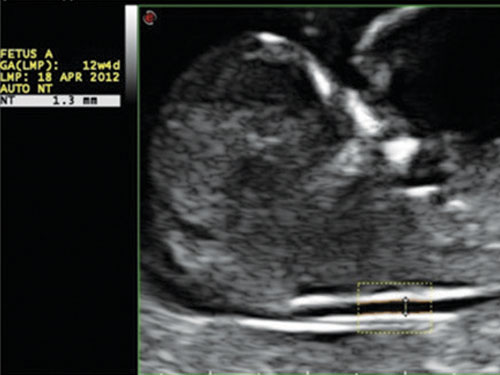

AutoNT: Automatické měření nuchální translucence (NT).

Díky své výkonné platformě Windows ™ 10 se Esaote MyLab ™ X7 zaměřuje na zkrácení doby vyšetření a lepší pracovní postupy pomocí široké škály automatických procesních funkcí „nulového kliknutí“ pro zobrazování, dopplerovské zpracování, následné zpracování, měření, archivaci a připojení. Díky zpracování „nulovým kliknutím“ lze nyní rychle a snadno provádět srdeční ejekční frakci nebo fetální nuchální translucenci.